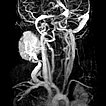

The girl is now 24 months old and the mass has not regressed. It is visible from the outside and causes the patient clear pressure pain. Dynamic contrast-enhanced MR angiography shows the intense enhancement of the infantile hemangioma. The main venous drainage is via the external jugular vein, which shows a relevant stenosis of the outflow in the proximal area.